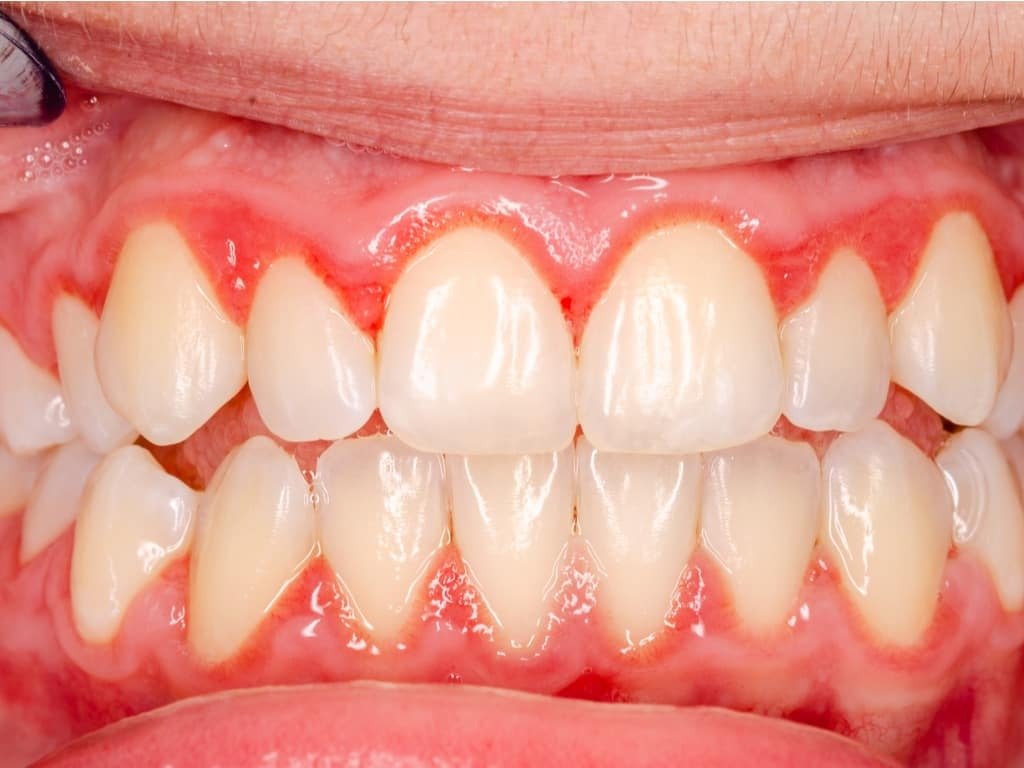

Présentation du patient : Homme de 38 ans, non-fumeur, en bonne santé générale. Consulte pour des saignements gingivaux spontanés depuis 8 mois. Hygiène bucco-dentaire insuffisante, sans habitude de fil dentaire ou de brossette interdentaire.

Problématique identifiée : Le sondage révèle une poche profonde de 8 mm en mésial de la 36 (première molaire mandibulaire gauche). Le cliché rétro-alvéolaire montre une lésion angulaire en mésial de la 36, avec présence visible de trois parois. La dent est non mobile. Pas d’atteinte de la furcation.